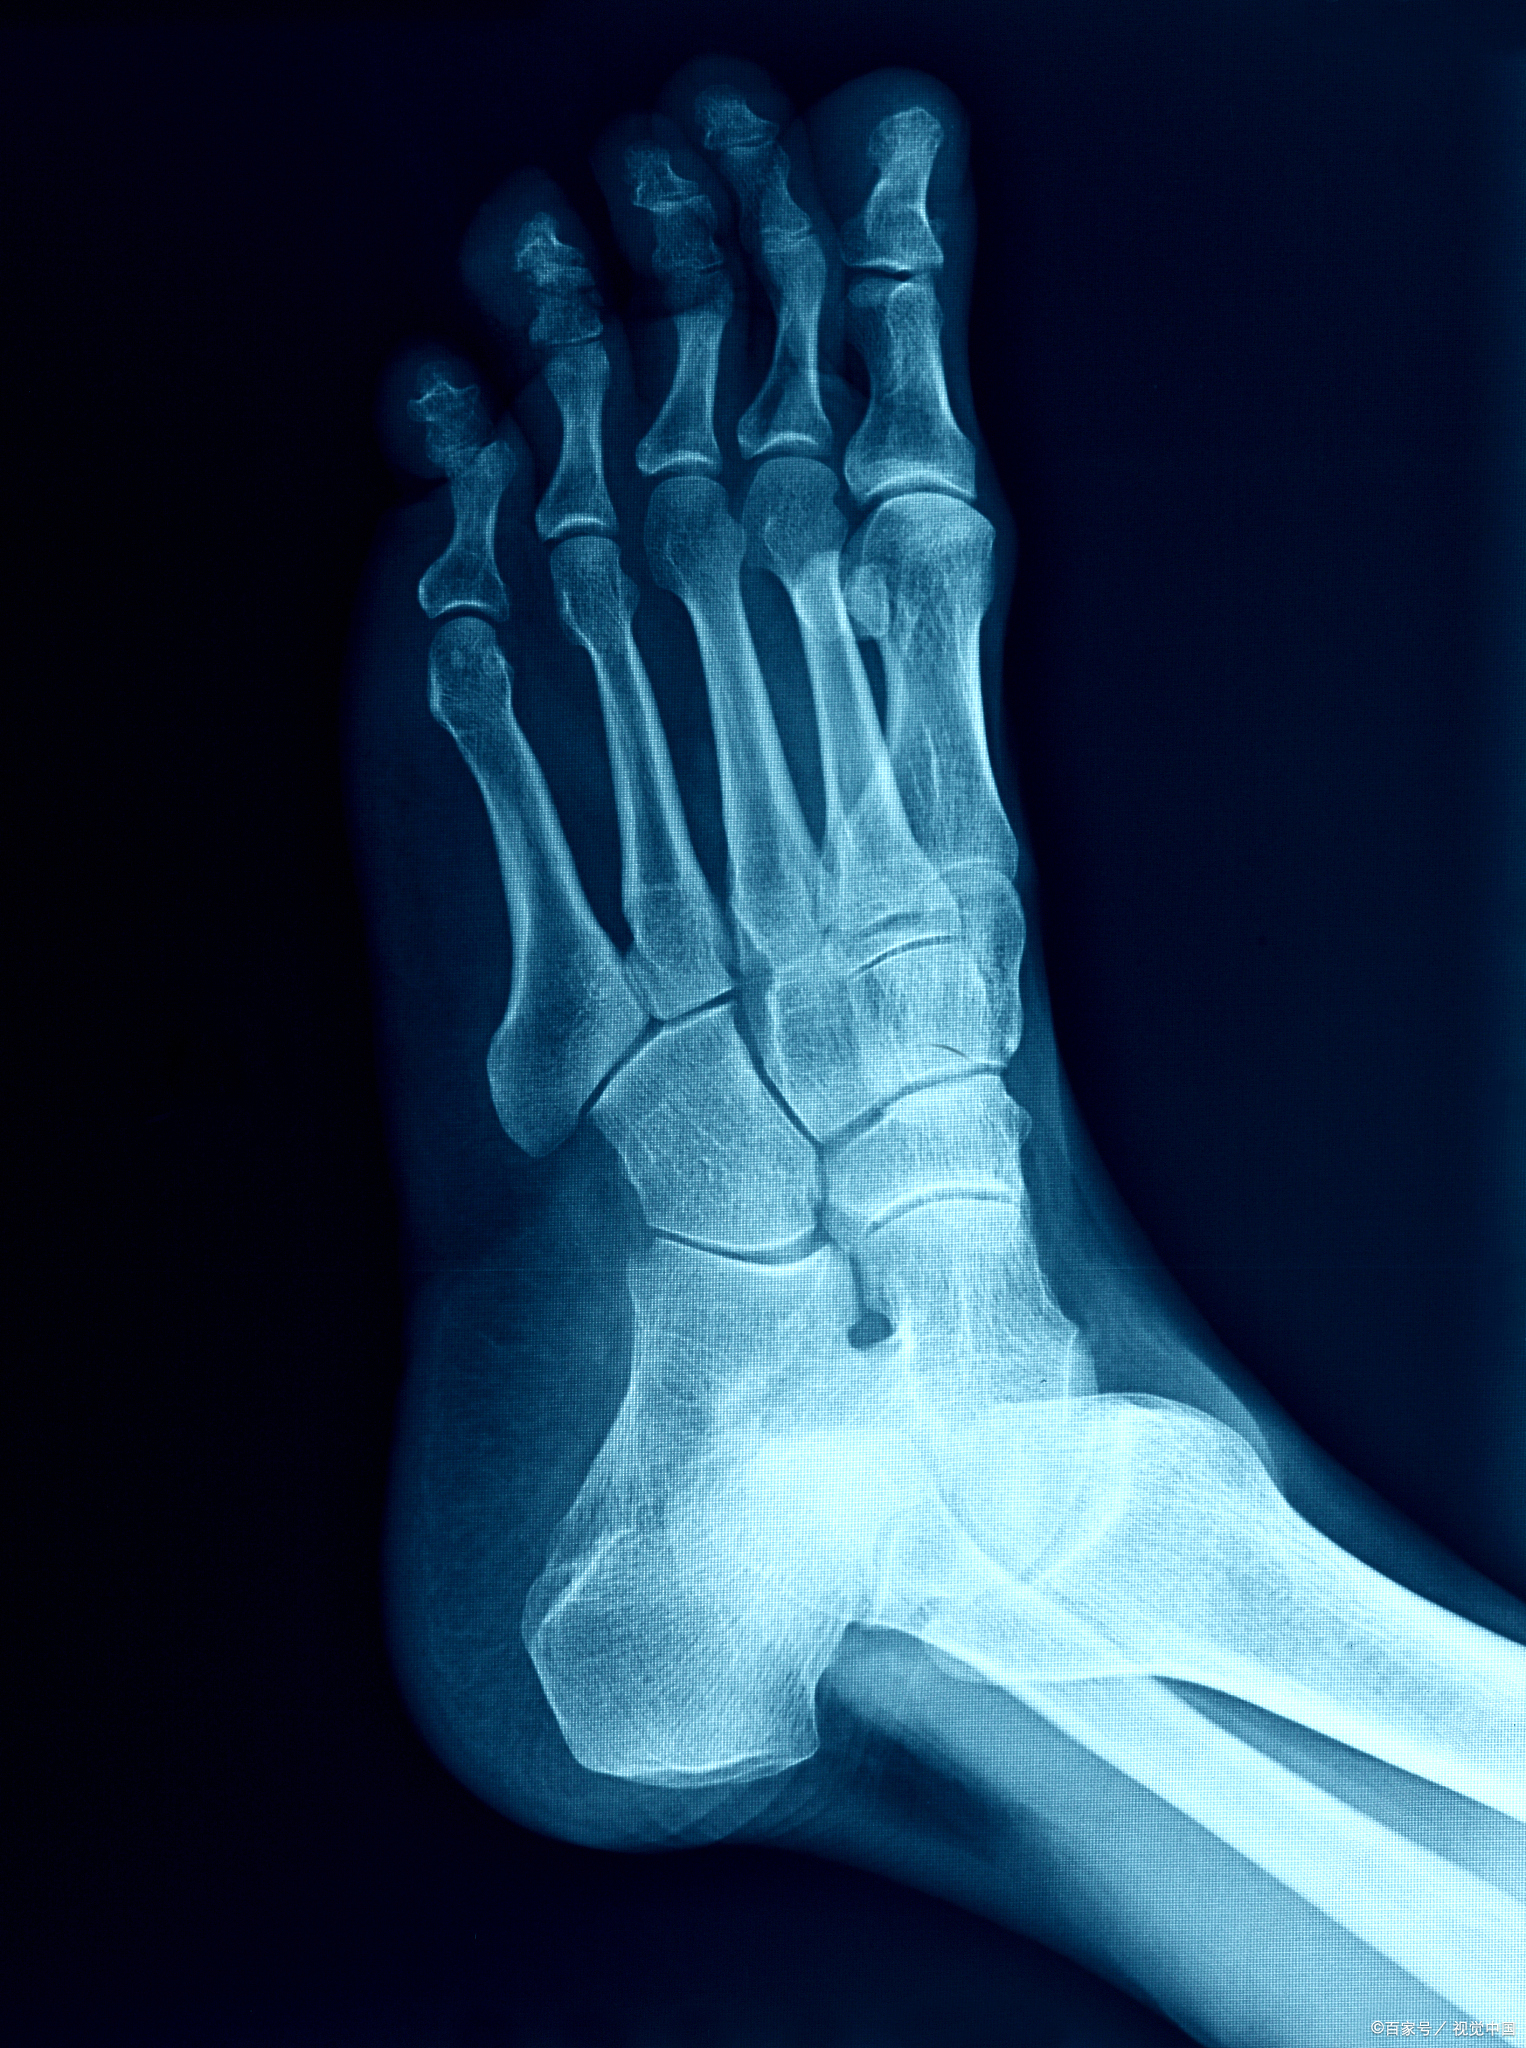

8%;尿酸:ua 375μmol/l;左踝关节正侧

痛风是由于尿酸结晶在踝关节的液体中积聚,尿酸是通过代谢某些类型的

踝关节痛风怎么办?踝关节痛风如何治疗防治

痛风往往从脚的关节痛起,最常见的就是跖趾关节,其次是脚踝关节,逐渐

脚踝关节尿酸盐结晶溶解转化